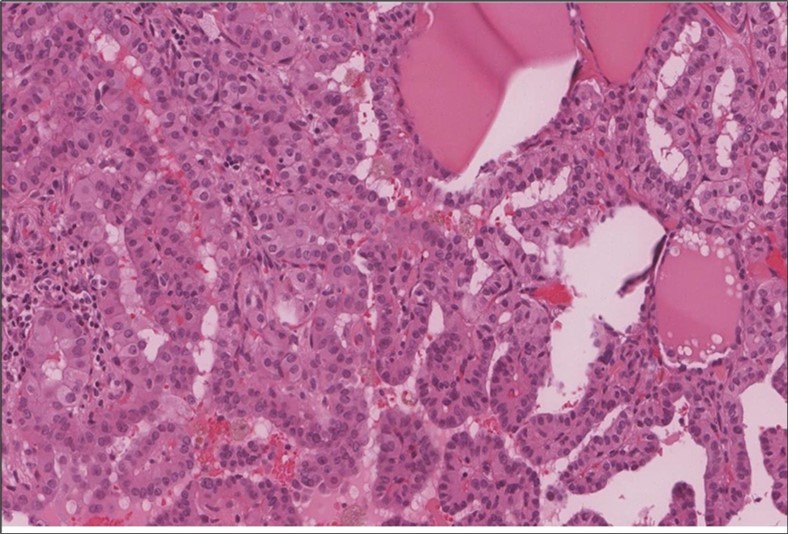

When diagnosing thyroid swelling, imaging studies have been helpful in differentiating malignant from benign tumors with US being used as an initial evaluation tool when assessing thyroid nodules. Tumors are categorized based on composition, echogenicity, shape, margin and echogenic foci into added scores determined by the TI-RADS system, which determines the need for FNA 13. Other imaging modalities include MRI and CT. However; radiological assessment does not distinguish between the types of thyroid cancer, and therefore FNA and biopsy are of crucial importance 3, 6. On a pathologic sample, LMS appears as spindled eosinophilic cells with elongated blunt-ended or cigar-like nuclei arranged in fascicles 2, 7 (Figure 1, Figure 2, Figure 3). Despite the unique microscopic morphology, LMS cannot be distinguished from other spindle cell tumors such as spindle cell variant of medullary thyroid cancer, anaplastic thyroid

Figure 3.Left thyroid The malignant looking cells are showing diffuse atypia, mitosis and hyper-chromatic nuclei, some remaining follicles could be noted as well (H&E, ×400).

cancer, or other metastatic tumors without further testing with genetic or molecular studies 3, 7. Immunohistochemical testing plays a vital role in differentiating LMS from such similar tumors as it stains positive for vimentin and smooth muscle actin (SMA), and is variably positive for HHF35, desmin (50%-100%), and H-caldesmon 3, 6. Moreover, there were no reported cases where thyroid LMS stained positive for thyroglobulin, cytokeratin, calcitonin, chromogranin, or protein S100 3. Our patient’s left thyroid biopsy showed the characteristic microscopic features and was positive for SMA, desmin, caldesmon, P63 with patchy EMA (Figure 1, Figure 2, Figure 3, Figure 4) as well as her liver biopsy (Figure 5, Figure 6, Figure 7); whereas her right thyroid showed clear papillary thyroid cancer cell features (Figure 8, Figure 9).